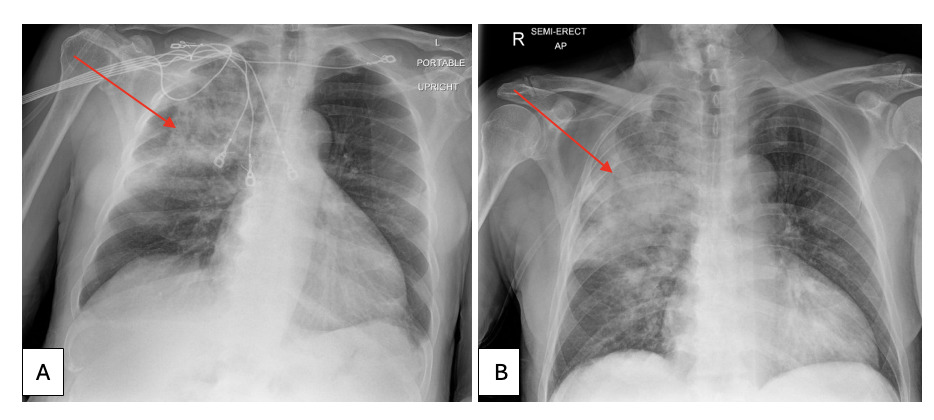

On arrival, he presented with a blood pressure of 127/55, a respiratory rate of 20 breaths/min, and an oxygen saturation of 89% on a high-flow nasal cannula. The patient was not in acute distress and auscultation of the lungs was unremarkable. Laboratory test results revealed a leukocyte count of 14.5 x 109 cells/L (reference, 4.0-10.7 x 109 cells/L) with neutrophilic predominance, hemoglobin of 8.7 g/dL (reference, 13.3-17.5 g/dL), procalcitonin of 3.88 ng/mL (reference, <=0.10 ng/mL) and creatinine of 1.95 mg/dL (reference, 0.71-1.16 mg/dL). Urinalysis was positive for 2+ protein and 3+ blood. Additionally, an acid-fast bacillus (AFB) test was obtained. Chest radiography (CXR) showed airspace and interstitial opacification of the right upper lobe with trace left pleural effusion with considerable worsening in the degree of right upper lobe consolidation with newly found infiltrate in the medial aspect of the right lower lung zone and left lung base in a subsequent CXR a day later (Figure 1). Computed tomography angiography of the chest also confirmed dense consolidations in the right upper lobe with scattered ground-glass opacities, concerning for multifocal pneumonia (Figure 2).

_computed_tomography_revealing_dense_consolidation_opacities_(arrow)_in_the_right_upper.png)